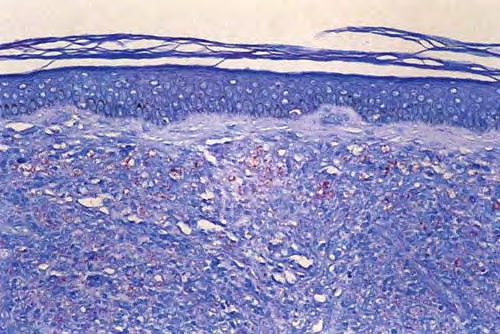

Lentigo maligna melanoma = ميلانوم الشامة الخبيثة Lentigo Maligna Melanoma Lentigo maligna, previously referred to as melanosis circumscripta preblastomatosa of Dubreuilh and also as melanotic freckle of Hutchinson [or Hutchinson’s melanotic freckle (HMF), a term used currently in Australia for this condition], accounts for about 10% of melanomas and typically occurs on the chronically exposed […]